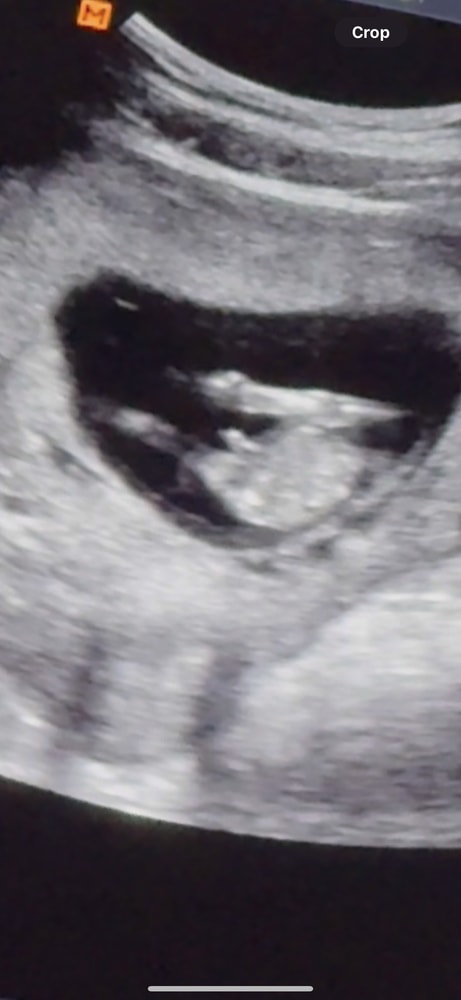

в Зачатие 3 месяца

Половой бугорок

Это не писюн, а половой бугорок, Из которого потом формируется либо писюн, либо клитор, так что пора рано вам пол, сейчас только гадания или кровь на выявление пола плода

В 12.2 рано делать выводы о половых органах,их ещё просто там нет

На таком сроке выводы про пол делают по углу наклона, строго в профиль. Ваши снимки не информативны для этого, в 12-13 недель между ног не смотрят, там пока одинаково всё у обоих полов. И да, на таком сроке и у девочек "огромный", только это не писюн. Сдайте кровь, если уж так не терпится узнать.

На таком сроке половые органы у плода м и ж одинаково выглядят. Это как трубка такая. Определить пол только по наклону бугорка можно

Таро Расклады на зачатие , 12,2